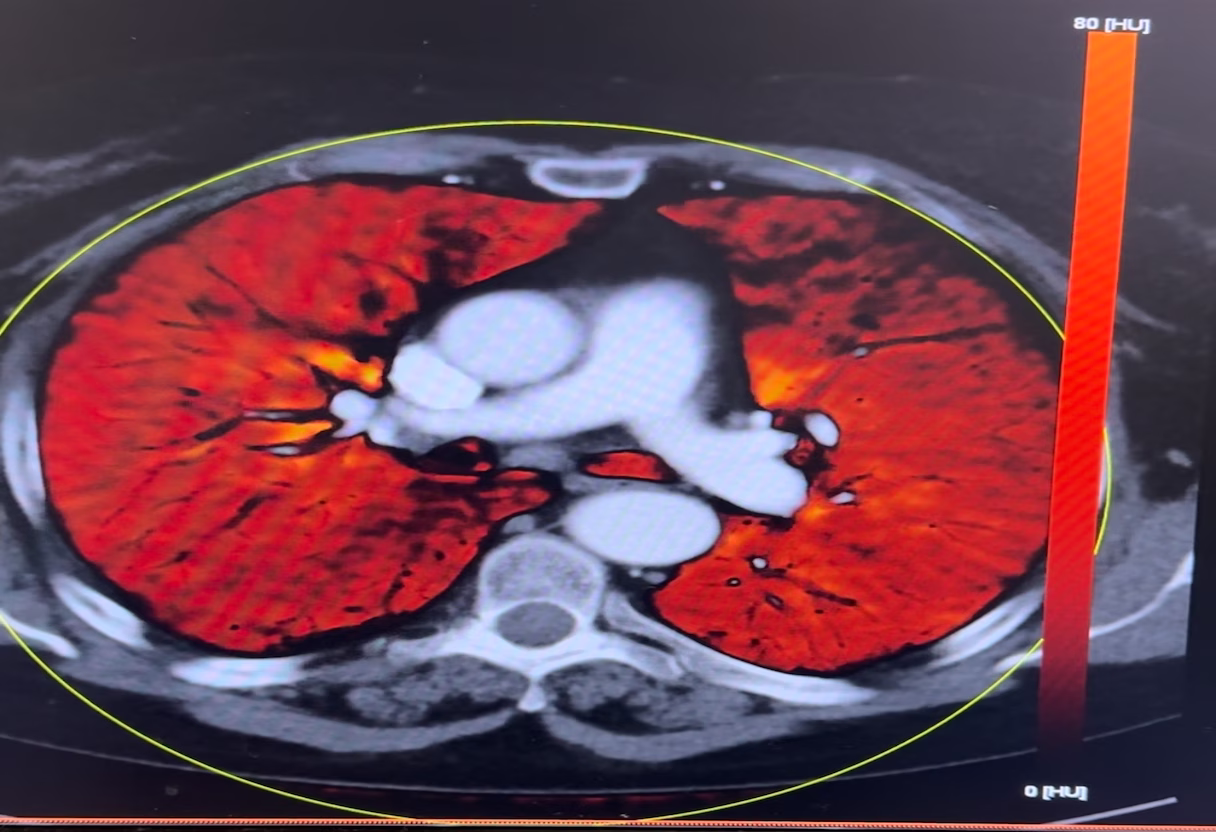

Comprehensive education for new and experienced staff, including advanced CT, protocol optimization, cardiac enhancement and dual-energy techniques.

Get real-time expert guidance for CT-guided biopsies, ablations, and IR cases. Connect via virtual connection, phone, or screen-share—so you’re never alone with a challenging scan.

Troubleshoot scans, adjust settings, and optimize protocols with live remote support for Siemens and GE systems. Perfect for new or experienced technologists seeking workflow improvements.